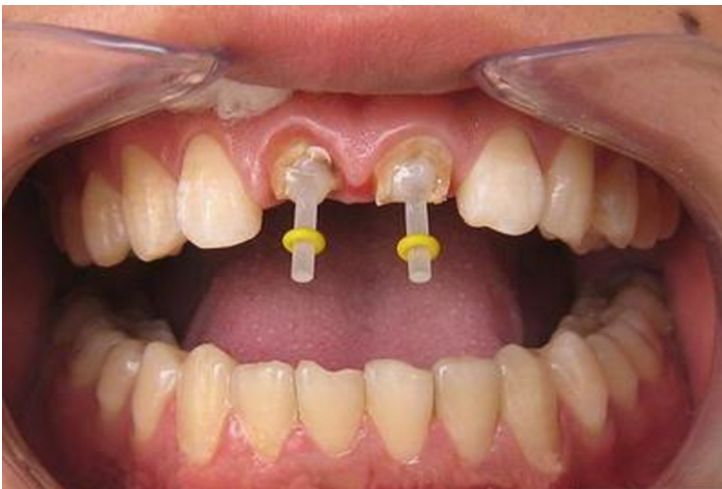

一些人在进行根管治疗后,会进行牙齿打桩。牙齿打桩是指在患者牙齿缺损较大,或因为外伤等原因只剩下牙根时,因剩下的牙齿过短或力量过于薄弱,不能用修复体直接修复,需要给牙根里打桩,加固并延长折断的牙齿,以使假牙能获得足够的力量固定。下面口腔专家给大家具体介绍一下牙齿打桩的相关知识。

牙齿打桩是指插入根管内的部分,利用摩擦力和粘固力、粘接力获得固位,进而为最终修复体提供固位。

牙齿桩的长度应该大约有牙槽骨支持的根长的1/2,即骨内桩长度大于骨内根长度的1/2,这样桩的末端不至于离牙槽脊太近,极大程度的减少根折。

一般来说,在桩材料强度足够的条件下,桩的直径在1/4到1/3根径范围内都对牙根的抗折性无明显影响。